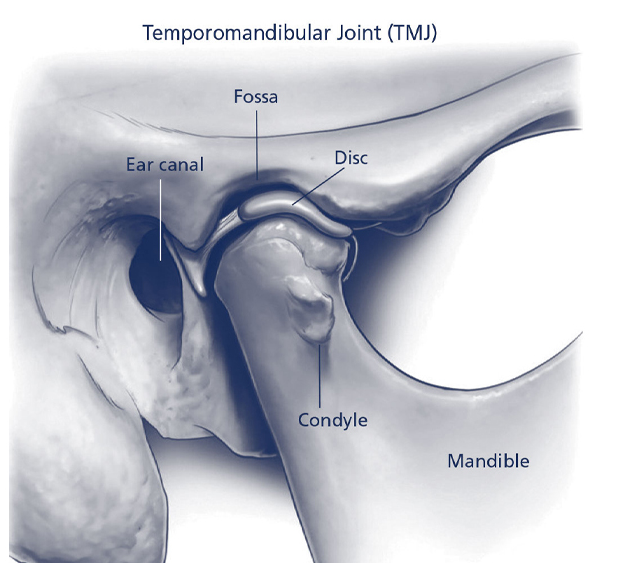

T M J